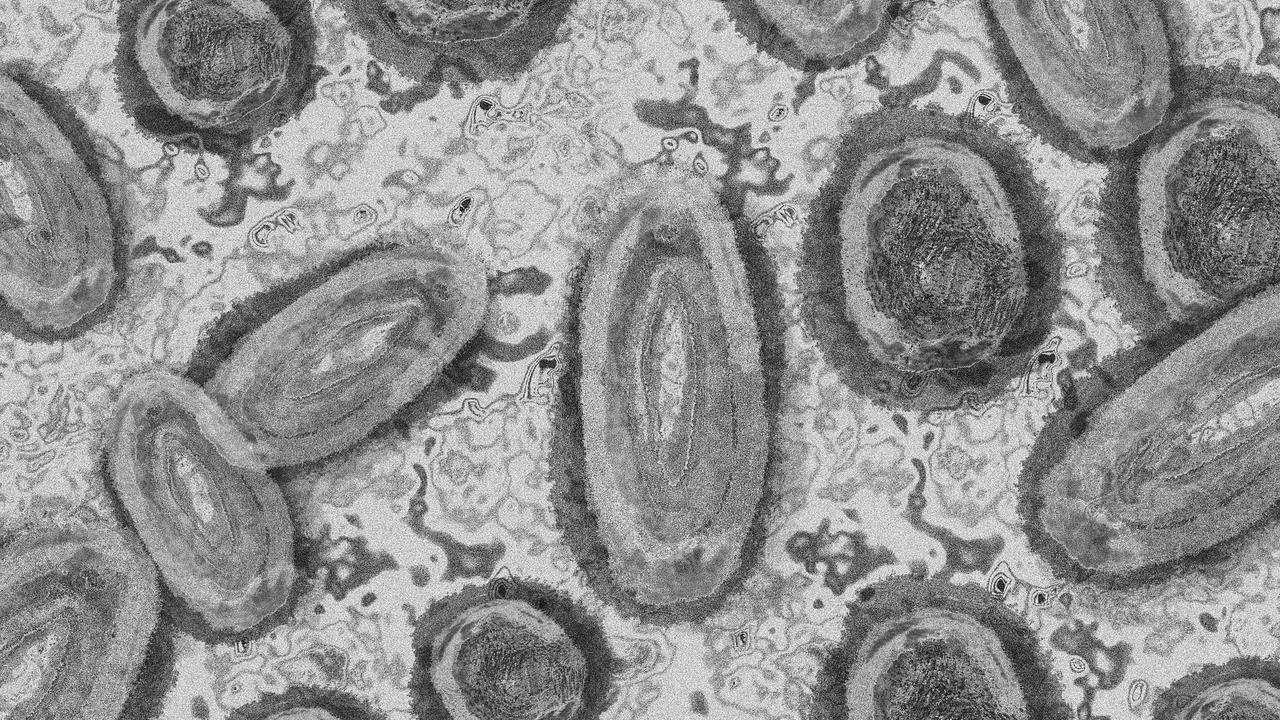

Dalam sebuah penelitian yang dilakukan ilmuwan Portugal ditemukan bahwa ada sejumlah perubahan kecil dalam kode genetik, varian gen minor, dan gen yang hilang dari virus cacar monyet yang menular pada Mei lalu. Hal tersebut menurut sebuah penelitian yang diterbitkan di Nature Medicine.

“Sangat tidak terduga menemukan begitu banyak mutasi pada virus cacar monyet 2022,” kata Joao Paulo Gomes dari Institut Kesehatan Nasional di Lisbon dan salah satu penulis laporan tersebut mengutip Bloomberg.

“Faktanya, mengingat karakteristik genom dari jenis virus ini, tidak lebih dari satu atau dua mutasi yang mungkin muncul setiap tahun.”

Virus monkeypox lebih stabil dan lebih lambat bermutasi dibandingkan virus Corona penyebab COVID-19. Di masa lalu, monkeypox tidak menyebar dengan mudah dari orang ke orang.